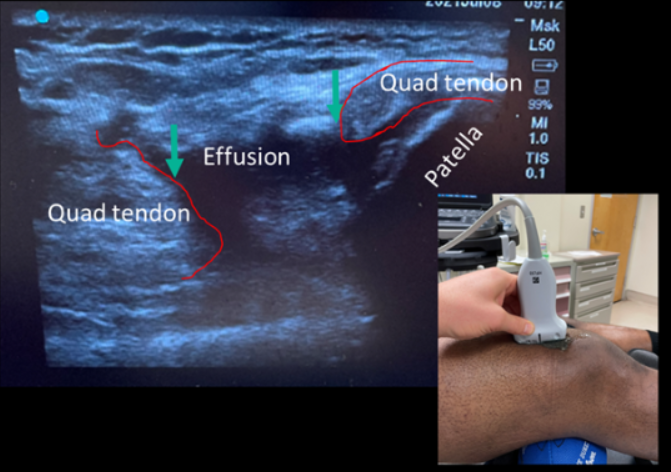

A 32-year-old male patient presented to the emergency department due to left knee pain. He was playing basketball when he came down from a vertical jump onto his left leg. He stated his kneecap appeared to be displaced laterally. On examination, patient had decreased range of motion of the left knee, tenderness on palpation of the lateral and medial aspect of the knee, and he was unable to extend his knee.

Jump, Land, and Tear